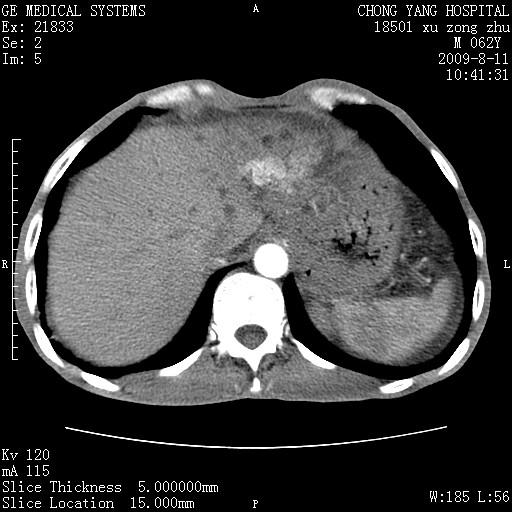

以下是引用杀毒软件在2009-8-11 16:35:00的发言:[br]肝内胆管扩张局限于左叶,胆管内有结石伴肝外胆管结石,胆管壁增厚呈弥漫性并发腹腔积液,胰腺边界模糊。[br][br]考虑---胆总管及肝内胆管结石继发胆管炎及胰腺炎,左肾下极囊肿,腹水。

以下是引用zjzjr在2009-8-11 17:35:00的发言:[br]肝内胆管扩张局限于左叶,胆管内有结石伴肝外胆管结石,胆管壁增厚呈弥漫性并发腹腔积液。[br][br]考虑---胆总管及肝内胆管结石继发胆管炎,左肾下极囊肿,腹水。